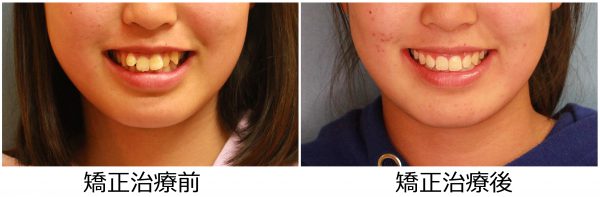

13歳 女性 「 八重歯 出っ歯を 治したい」 ( 上下顎叢生)

13歳の女性 です。

「八重歯と出っ歯をなんとかして欲しい」との事で来院されました。

前歯の段差が激しく、”八重歯”の状態です。

前歯が前に傾斜しているため

”出っ歯”も気になるとの事です。

叢生を伴う 上顎前突症 です

矯正治療のために 上下左右の 抜歯を行い

段差を解消し、前歯を後方に移動させました。

2018年の7月7日にスタートして 2019年の11月2日に 終 了しました。

治療期間は 16か月でした。

歯ならびは綺麗に整い ”八重歯” と ”出っ歯” 感は解消されました。

口元がスッキリ しました。

口もとの 印象が 大きく変わり お母さんが一番喜ばれていました。

素敵な笑顔になりました! (#^.^#)

まだ 15歳 (^◇^)! この笑顔で

これから 素敵な青春をお過ごしください!

13歳 女性 叢生を伴う 上顎前突症 治療期間16か月 唇側矯正装置(ホワイトワイヤー)を使用した上下顎第一小臼歯抜歯治療 参考治療費 約65万円 (精密検査から終了まで) 矯正治療に伴う副作用の歯肉退縮、知覚過敏、失活、歯根吸収などは認められませんでした。